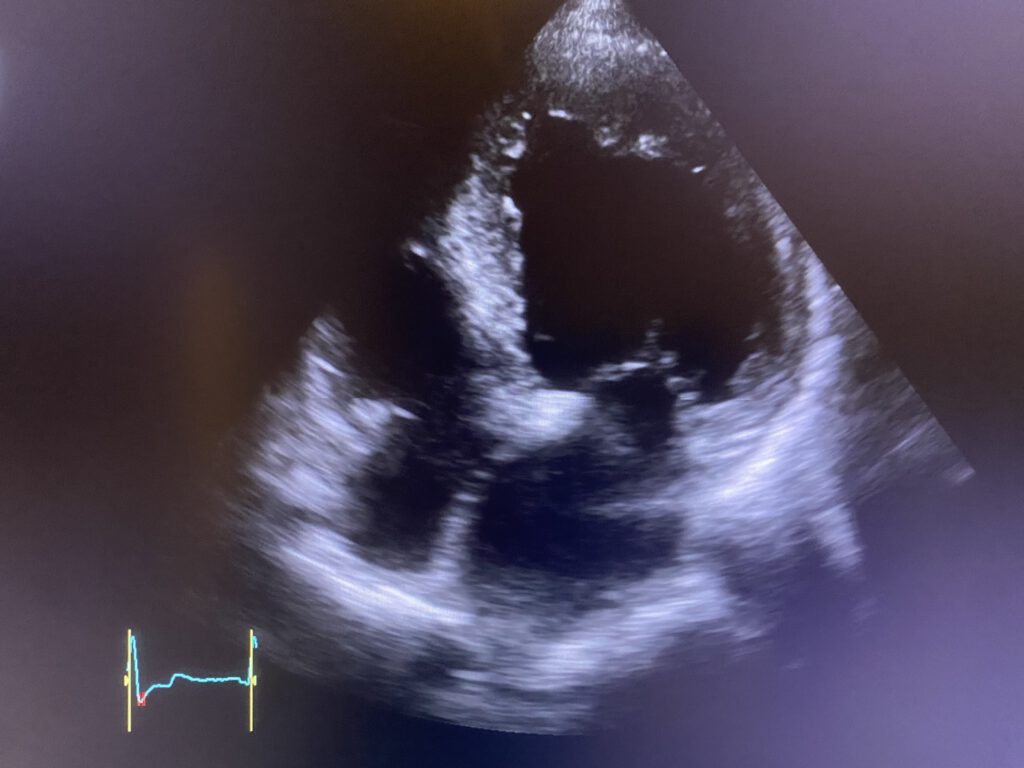

– Ultraschalluntersuchungen (Echokardiografie) von Herz,

- Kardio-Check (ausgiebige Anamnese, körperliche Untersuchung, Ultraschall von Herz, hirnversorgende Gefäße, EKG, ggf. Belastungs EKG

- Komplett-Check: (ausgiebige Anamnese, körperliche Untersuchung, Hautkrebsscreening, Stuhluntersuchung auf Mikroblutungen, Urinuntersuchung, grosse Blutuntersuchung, Ultraschall vom Bauch, Herz, hirnversorgende Gefäße, Schilddrüse, Lungenfunktionsuntersuchung, EKG, ggf. Belastungs EKG)